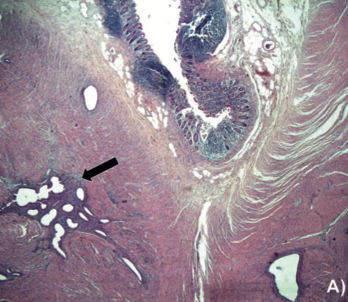

Imagen de portada

Resultados: Mujer de 35 años con dolor abdominal crónico de 4 meses de evolución. Se realiza estudio colonoscópico evidenciando lesión de 15 x 8 mm en ostium apendicular intususceptada al lumen cecal, y enteroclisis por tomografía axial computarizada (TC) que confirma IA. Se realiza una resección ileocecal laparoscópica demostrando la invaginación del apéndice con biopsia que muestra un foco de endometrioma.

Discusión: La IA es una condición infrecuente con una incidencia cercana al 0,01% en la población general. Las patologías benignas son la principal causa (77%), siendo la endometriosis la causa más frecuente.

Conclusión: La IA por endometriosis es anecdótica, con sintomatología poco específica. Los estudios disponibles pueden orientar adecuadamente la presencia de IA, sin embargo, en algunas ocasiones puede confundirse con patologías neoplásicas, en donde cobra importancia la cirugía para dilucidar la etiología.